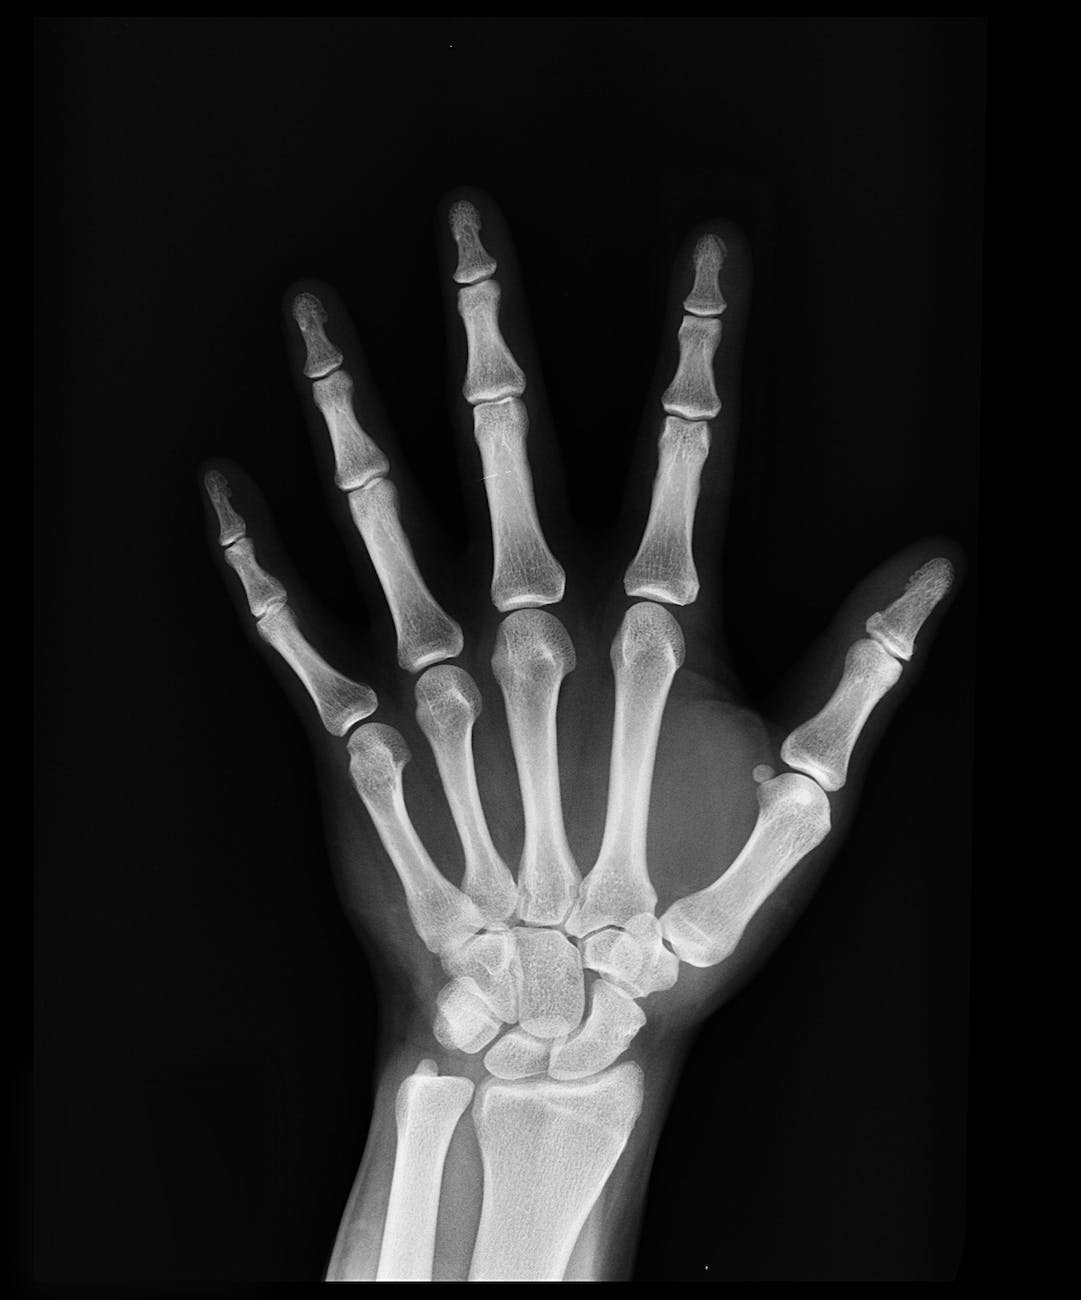

La Roentgenterapia o Röntgenterapia è un trattamento medico di radioterapia utilizzato come terapia in associazione contro numerose neoplasie e affezioni infiammatorie della cute. Essa è stata così denominata in onore dello scopritore dei raggi x, Wilhelm Conrad Röntgen nel 1896.

Essa si serve di un tipo di raggi X con lunghezza d'onda molto breve e quindi particolarmente penetrante, e mira a distruggere completamente il tumore cercando, quanto più possibile, di mantenere basso il rapporto tra la dose di radiazione somministrata al paziente e quella assorbita dal focolaio patologico in trattamento.